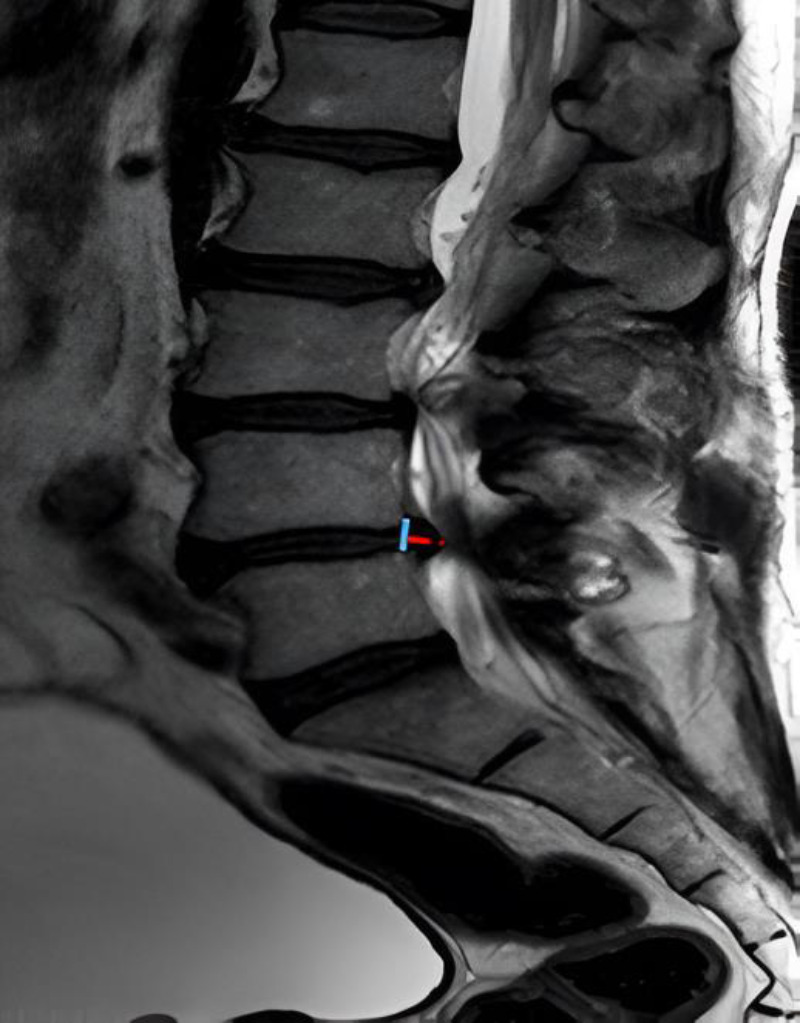

Methods: Imaging changes in patients who underwent indirect lumbar decompression and percutaneous posterior fixation were analyzed with one-year follow-up. Radiographic measurements were performed preoperatively and postoperatively (at one year), and the area of lumbar canal occupation and yellow ligament by nuclear magnetic resonance was compared preoperatively, at 48 hours post-surgery, and at one year. Radiographic measurements included disc height, foraminal height, total lumbar lordosis, and segmental lordosis. The VAS lumbar and lower limb scales and the Oswestry Disability Index (ODI) were used to assess clinical outcomes.

Results: A total of 21 male and 23 female patients underwent indirect decompression at 64 lumbar levels. A significant improvement was observed in the clinical evaluation of all patients' post-surgery (p < 0.001) in all radiographic parameters. There was an immediate increase in the lumbar canal at 48 hours (p < 0.001), which continued to increase at one year post-intervention (p < 0.05). The yellow ligament occupation area decreased at 48 hours (p < 0.001) and continued to decrease until one year (p < 0.01). Four complications were recorded, one of which was a posterior tract infection requiring open decompression.

Conclusion: Indirect decompression for degenerative lumbar disease provided successful clinical outcomes, including indirect expansion of the dural sac at 48 hours post-procedure, with progressive increase in the lumbar canal area at one-year follow-up.